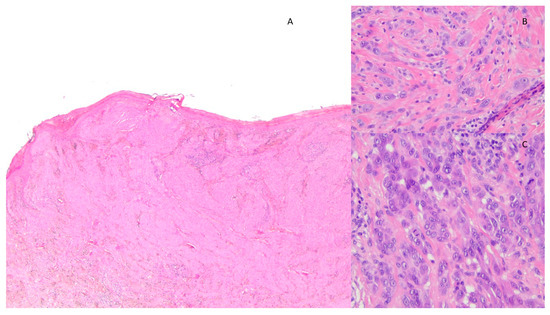

Figure 2.

Histological image of AST showing (A) compound melanocytic proliferation characterized by architectural asymmetry and hypercellular, irregular intradermal growth reaching the dermo-hypodermal border (EE 2×); (B) elements of spitzoid morphology with atypia such as anisonucleosis and nuclear pleomorphism (EE 40×); and (C) several mitoses in the deep dermal component (EE 40×).